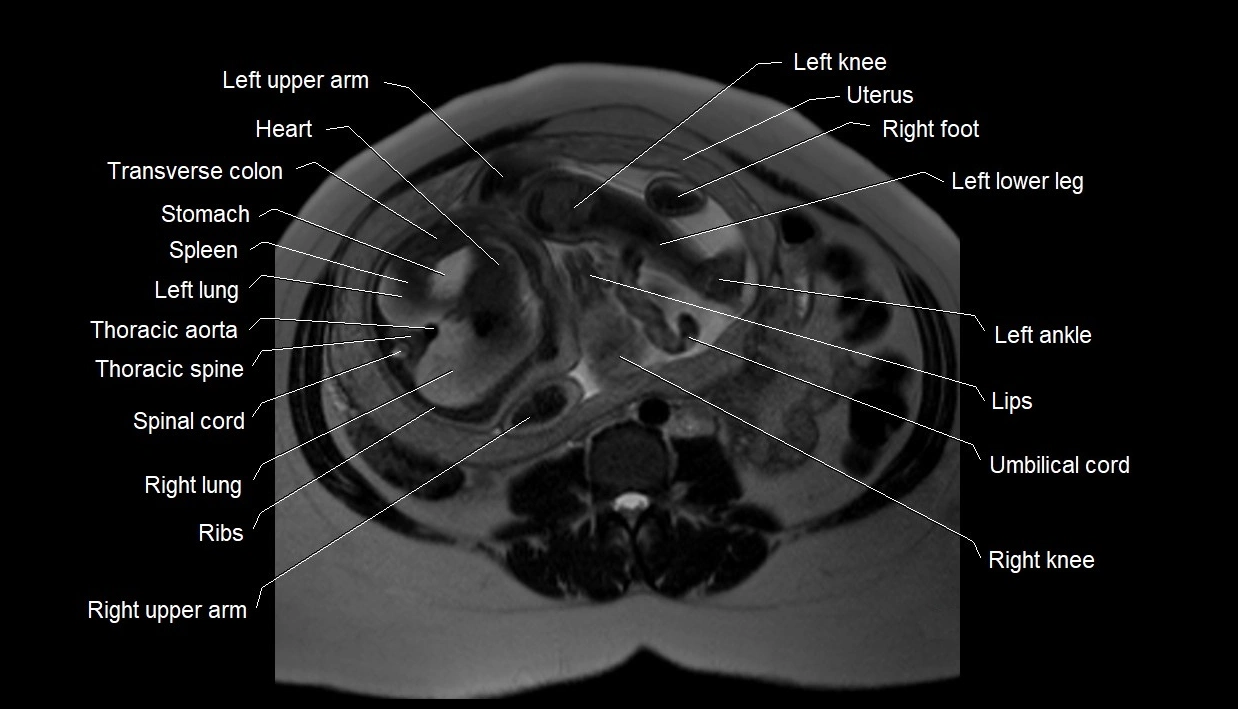

MRI Appearance

T2 HASTE (T2 GRE):

• Amniotic fluid shows very bright hyperintense signal

• Provides natural contrast against fetus and placenta

• Small particles (vernix) may appear as scattered hypointense foci within bright fluid

MRI image

image